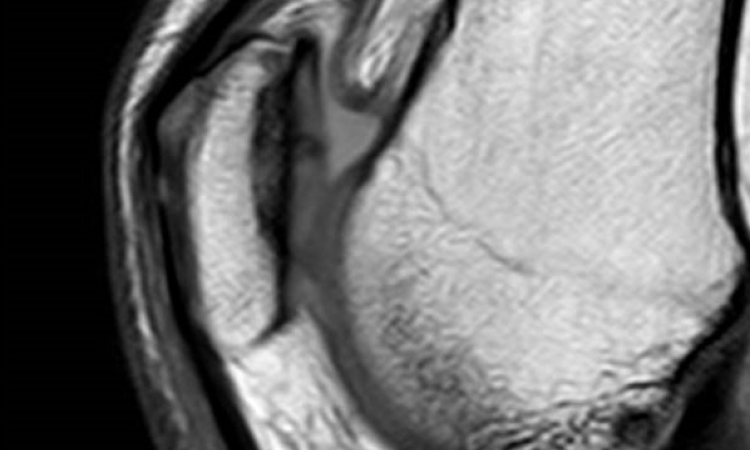

In vielen Fällen biete die Ultraschalldiagnostik eine Alternative zum Röntgenbild. So könnten sehr häufig vorkommende Handgelenksbrüche in neun vor zehn Fällen rein sonografisch diagnostiziert und kontrolliert werden. Bei Ellenbogenbrüchen ließen sich 70 Prozent und an der Schulter sogar drei Viertel der Röntgenbilder einsparen, so Ackermann. „Die Sonografie basiert auf ungefährlichen Schallwellen und hat auch bei intensiver Anwendung keine gesundheitsschädlichen Nebenwirkungen“, ergänzt der Experte.